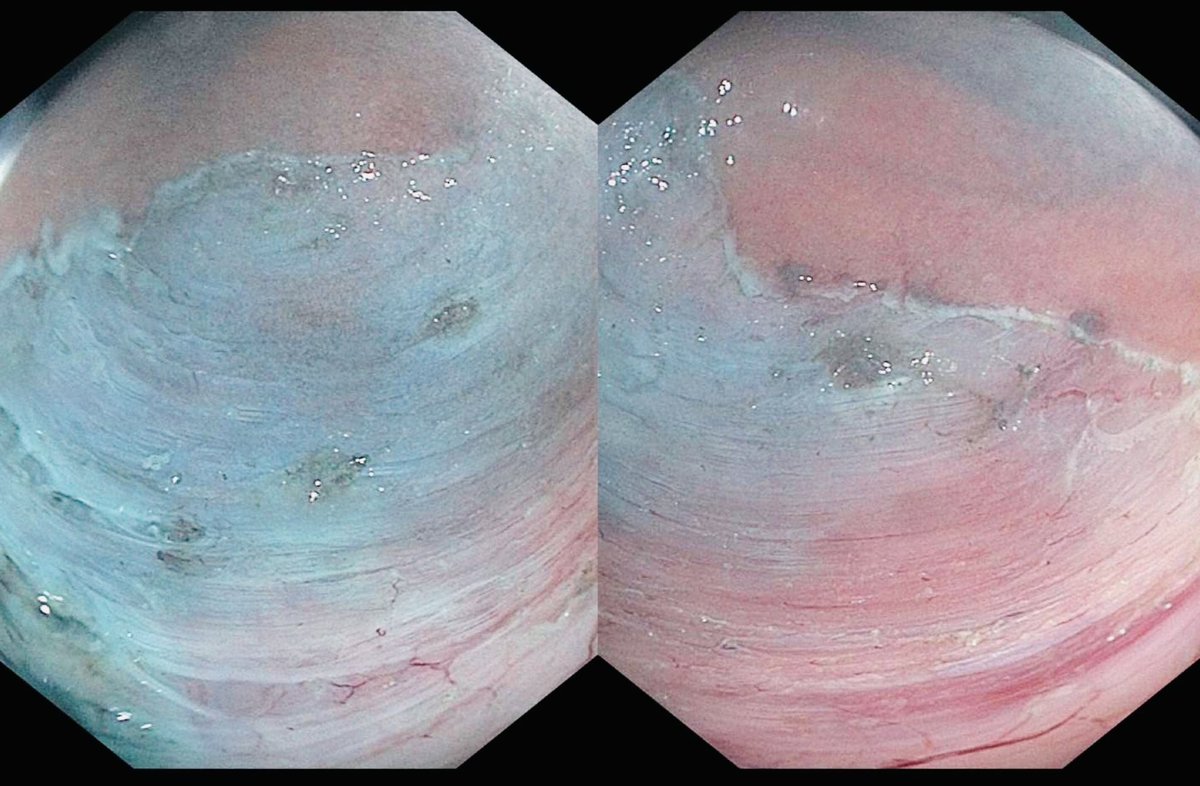

What an incredibly academic week at @SLUgastro! 🎓 We are very privileged 🙌 to have received a GI grand rounds from @NorioFukamiMD and to have hosted Dr. Vikesh Singh from @HopkinsGIHep 👨🏫 to give this year's Burton Memorial Lecture in addition to IM grand rounds @im_slu 🌟